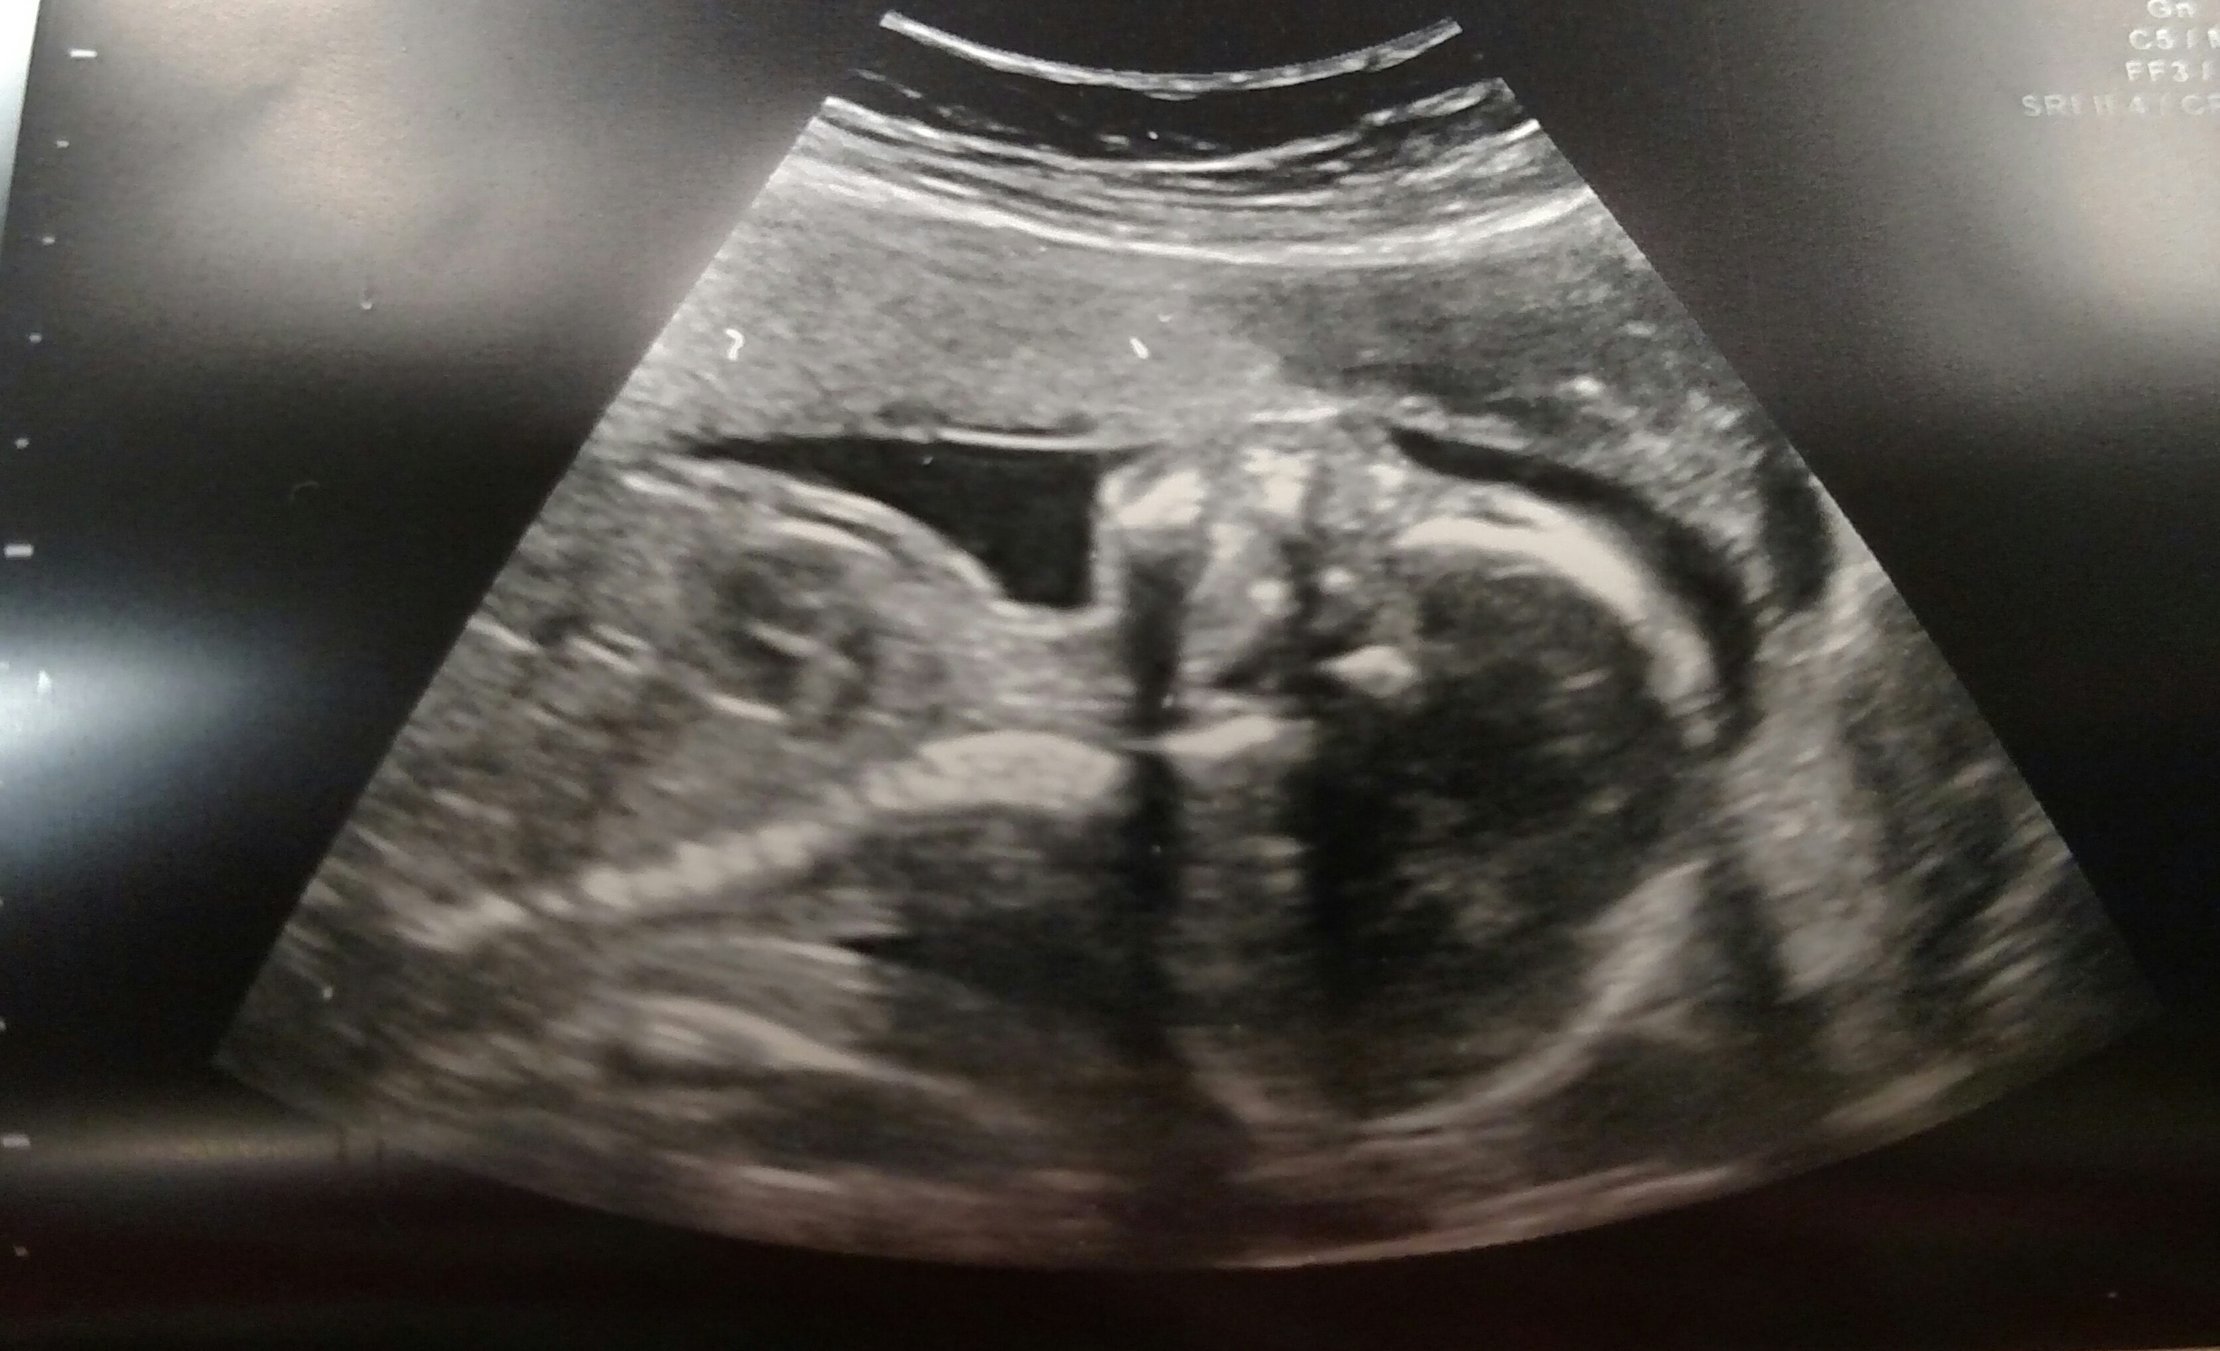

Had our anatomy scan today and found out we are having a baby boy!!